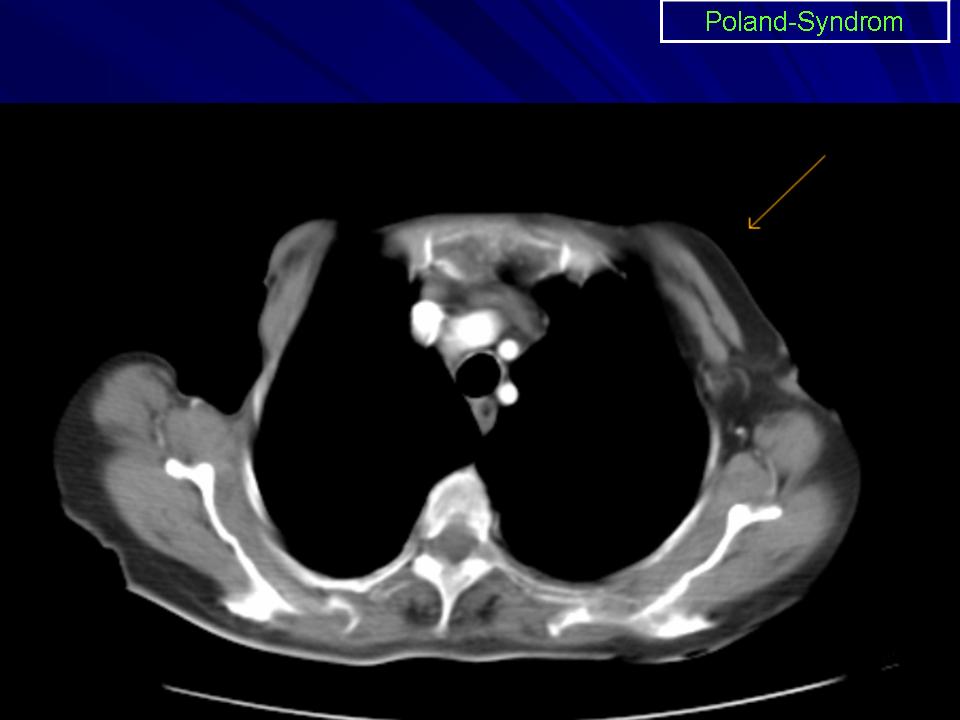

Синдром Поланда (СП) представляет собой комплекс пороков, включающий отсутствие большой и малой грудной мышц, синдактилию, брахидактилию, ателию (отсутствие соска молочной железы) и/или амастию (отсутствие самой молочной железы), деформацию или отсутствие нескольких ребер, отсутствие волос в подмышечной впадине и снижение толщины подкожно-жирового слоя. Отдельные компоненты этого синдрома впервые были описаны Lallemand LM (1826) и Frorier R (1839). Однако назван он по имени английского студента-медика Alfred Poland, который в 1841 году опубликовал частичное описание данной деформации. Полную характеристику синдрома в литературе впервые опубликовал Thompson J в 1895 году.